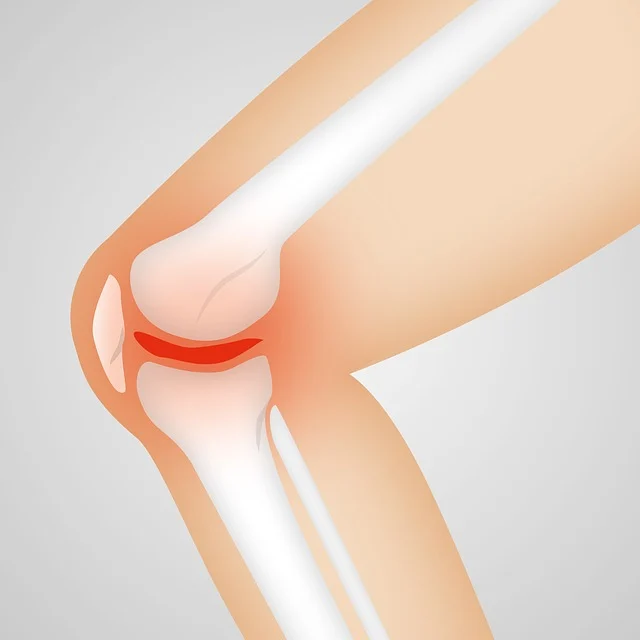

무릎 관절염은 무릎 관절을 덮고 있는 연골이 손상되면서 발생하는 퇴행성 질환입니다.

1기 관절염은 연골 손상이 시작된 초기 단계로, X-ray 검사에서 큰 변화는 보이지 않지만 환자는 뚜렷한 통증이나 뻣뻣함을 느끼기 시작합니다.무릎 관절염 1기 증상 초기 통증이 있으신 분들은 아래 통증 완화 방법을 아래에서 확인하시기 바랍니다.

5. 병원 진단과 검사 방법

병원에서는 다음과 같은 방법으로 1기 관절염을 진단합니다.

- X-ray : 관절 간격 변화 확인

- MRI : 연골 손상 여부 세밀 분석

- 관절 초음파 : 염증, 삼출액(물 찬 무릎) 여부 확인